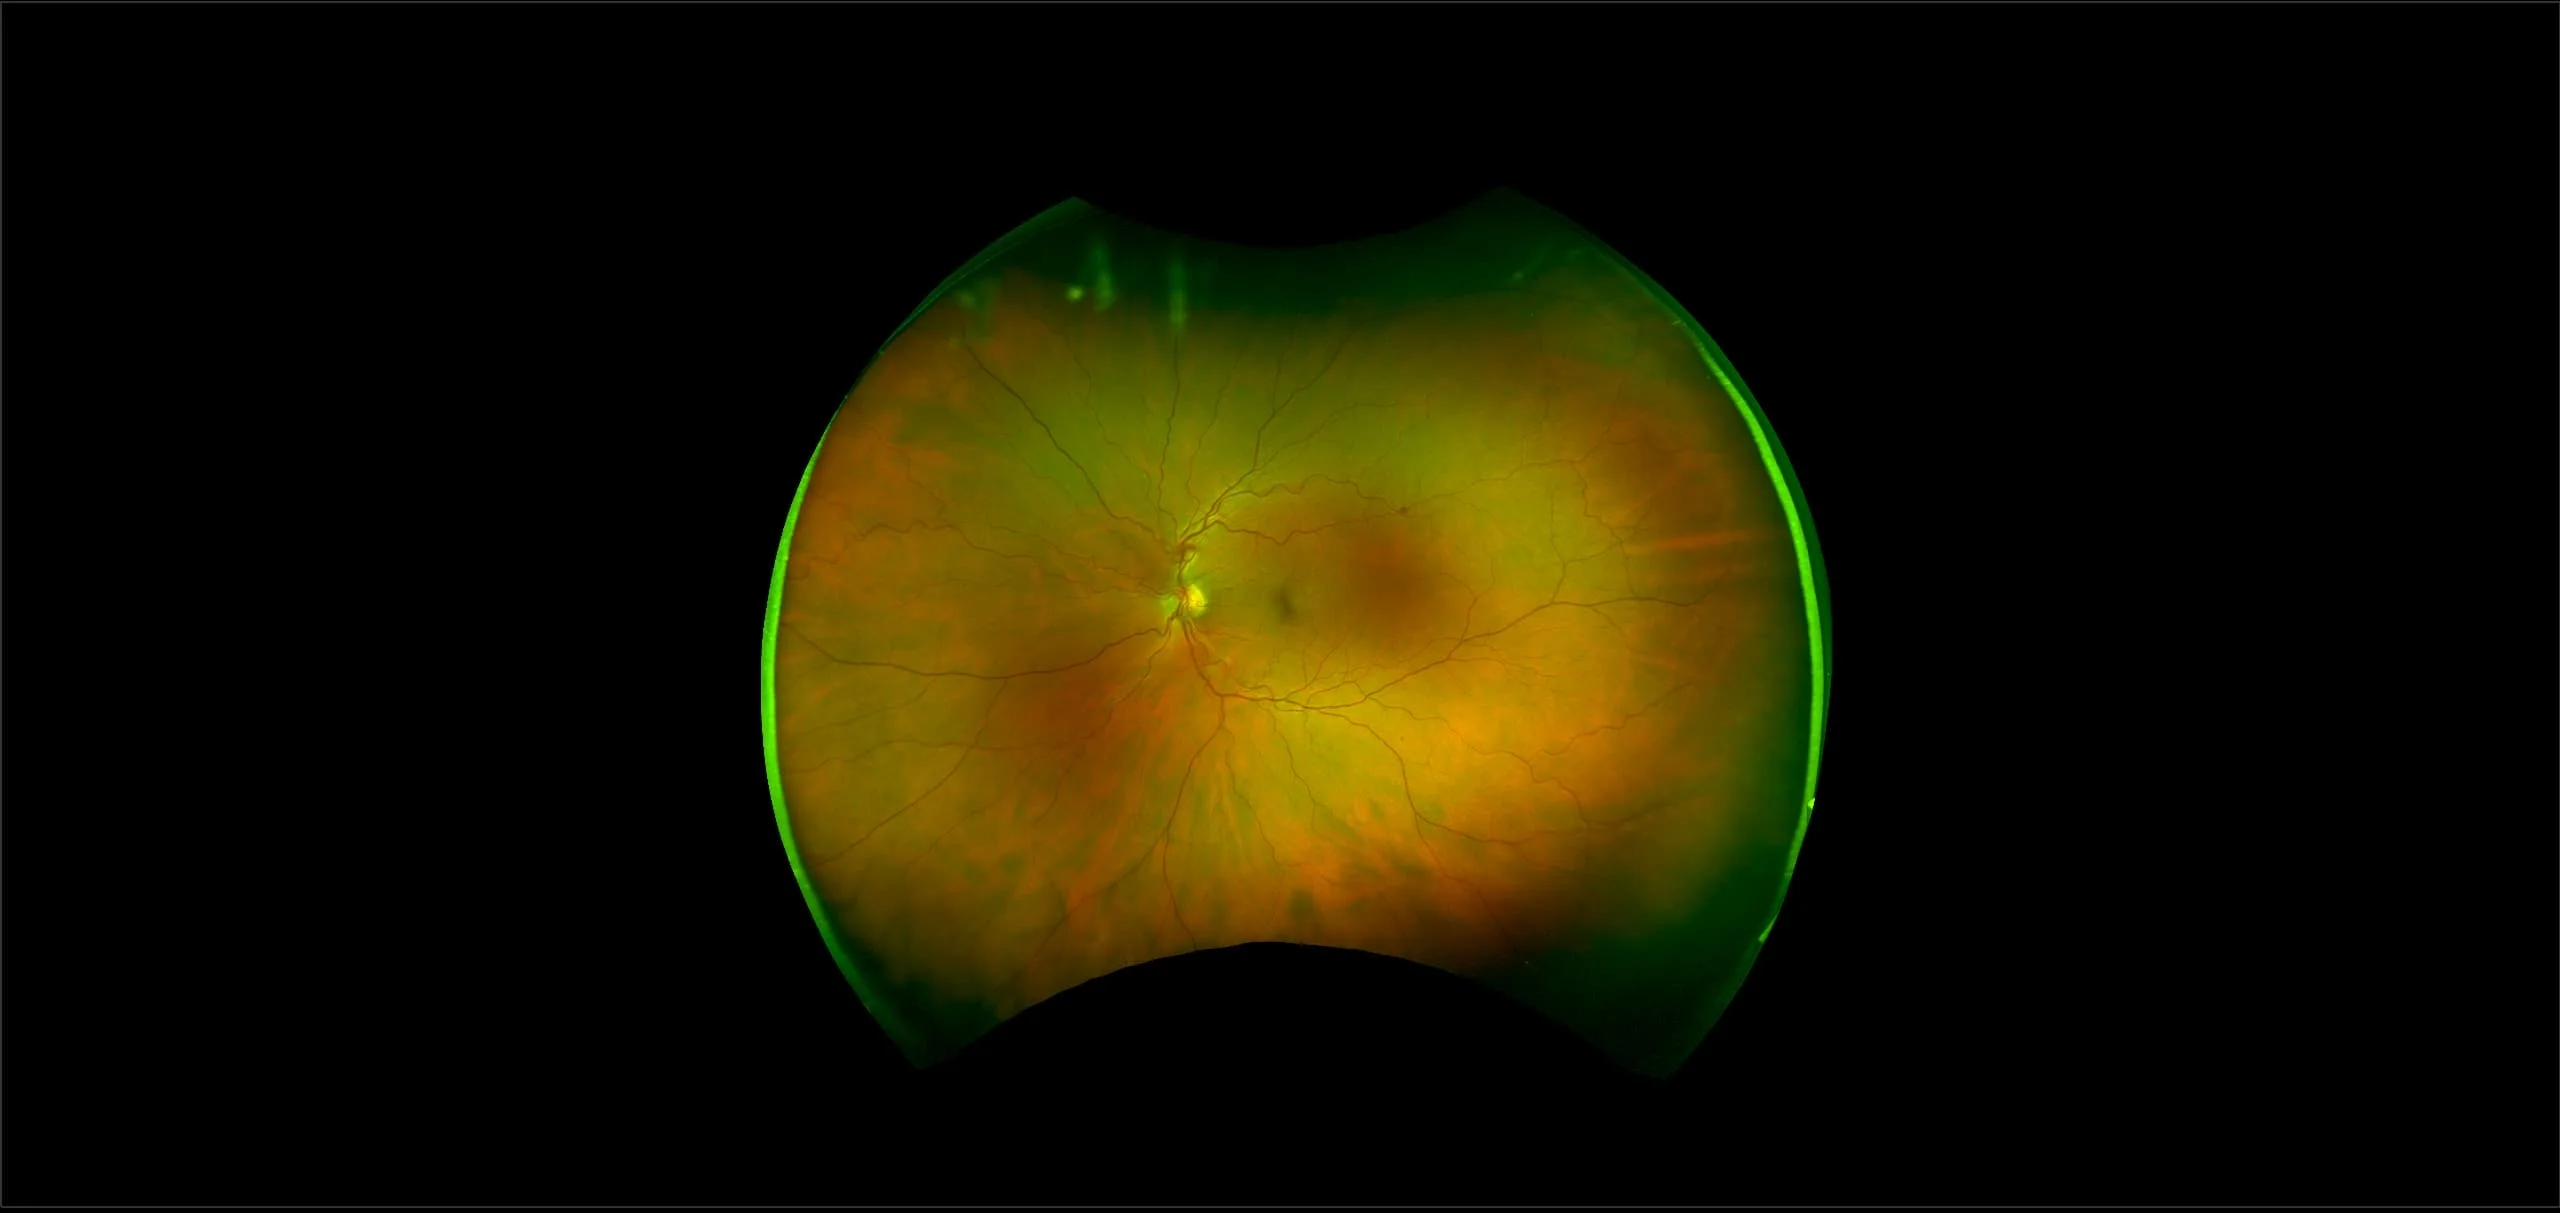

MonacoPro - Vitreous Floaters, RG, OCT

Vitreous floaters are microscopic collagen fibers within the vitreous that tend to clump and cast shadows on the retina, appearing as floaters to the patient.